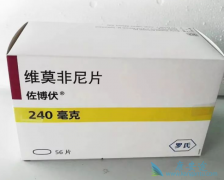

前列腺癌是现代男性非常常见的一种癌症恶性肿瘤,由于现代男性的生活和工作压力的增大,越来越多的前列腺癌患者开始出现,发病率不断上涨。如果前列腺癌到了晚期还没有进行及时治疗,很有可能导致肿瘤恶化转移,对于我们癌症患者来说,目前阿比特龙有着 ...